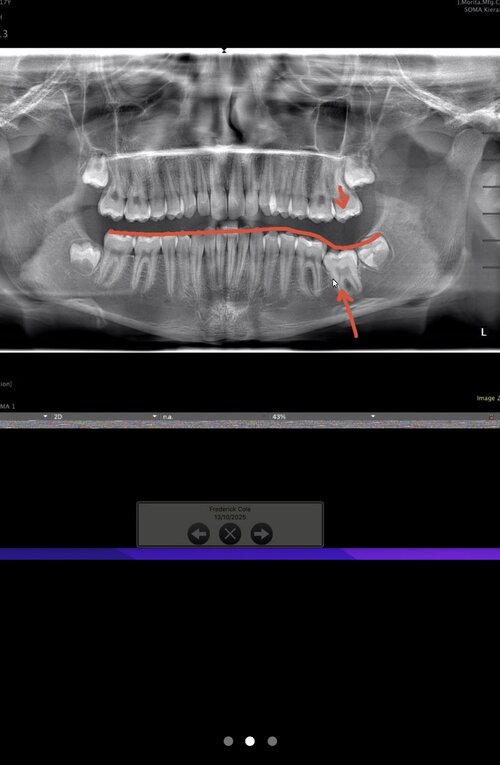

I have been recommended by the orthodontist to get my back left molar removed and potentially my wisdom teeth. He then said i should get 3 years of braces and some other shit. I feel like this is all bull shit, and he just wants to extort my parents' money. He said that because my back left molar is not coming through, my jaw could not be developing, but this contradicts everything I have seen on here with teeth extractions leading to recession. Could someone please help me